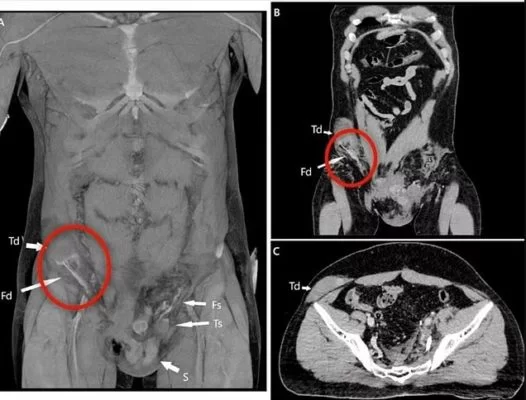

Depois de tratado, os médicos o levaram para fazer uma tomografia computadorizada que apontou onde estava o testículo deslocado. Foi necessária uma cirurgia de 1h30 para que o órgãos fosse colocado de volta ao lugar de origem.